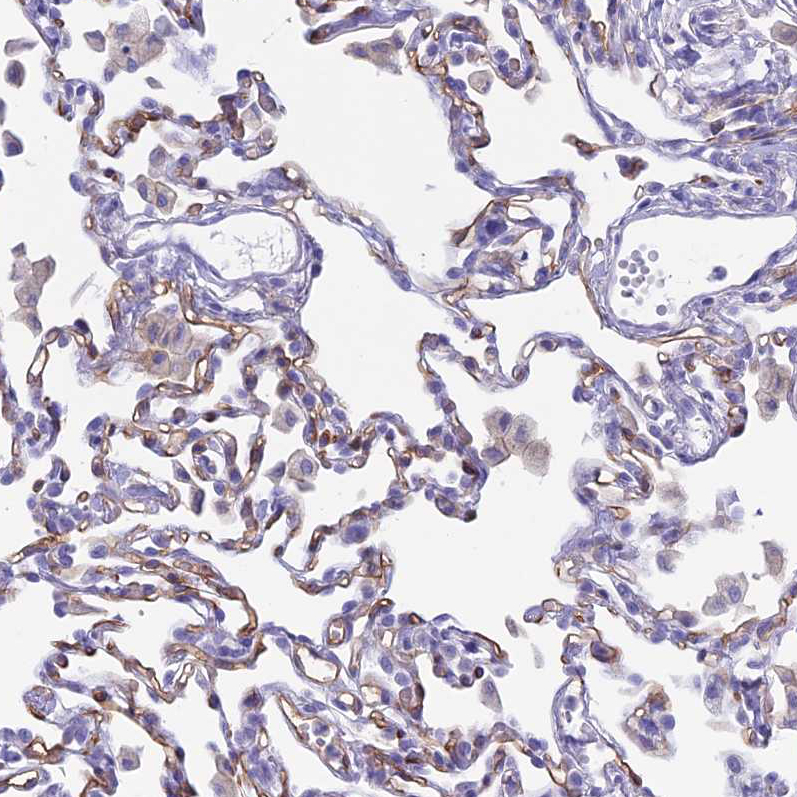

Immunohistochemistry analysis in human small intestine and liver tissues using HPA029298 antibody. Corresponding ACE RNA-seq data are presented for the same tissues.